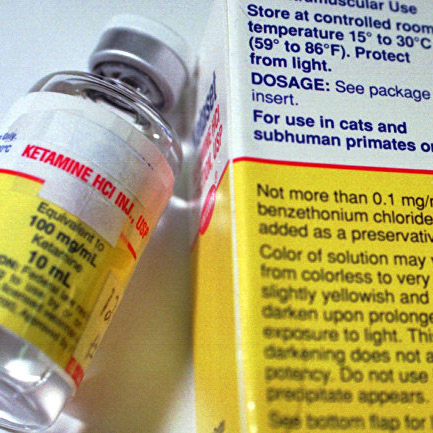

Исследования на животных свидетельствуют, что раковые клетки могут быть выведены из мозга и направлены в специально имплантированную капсулу с токсическими веществами.